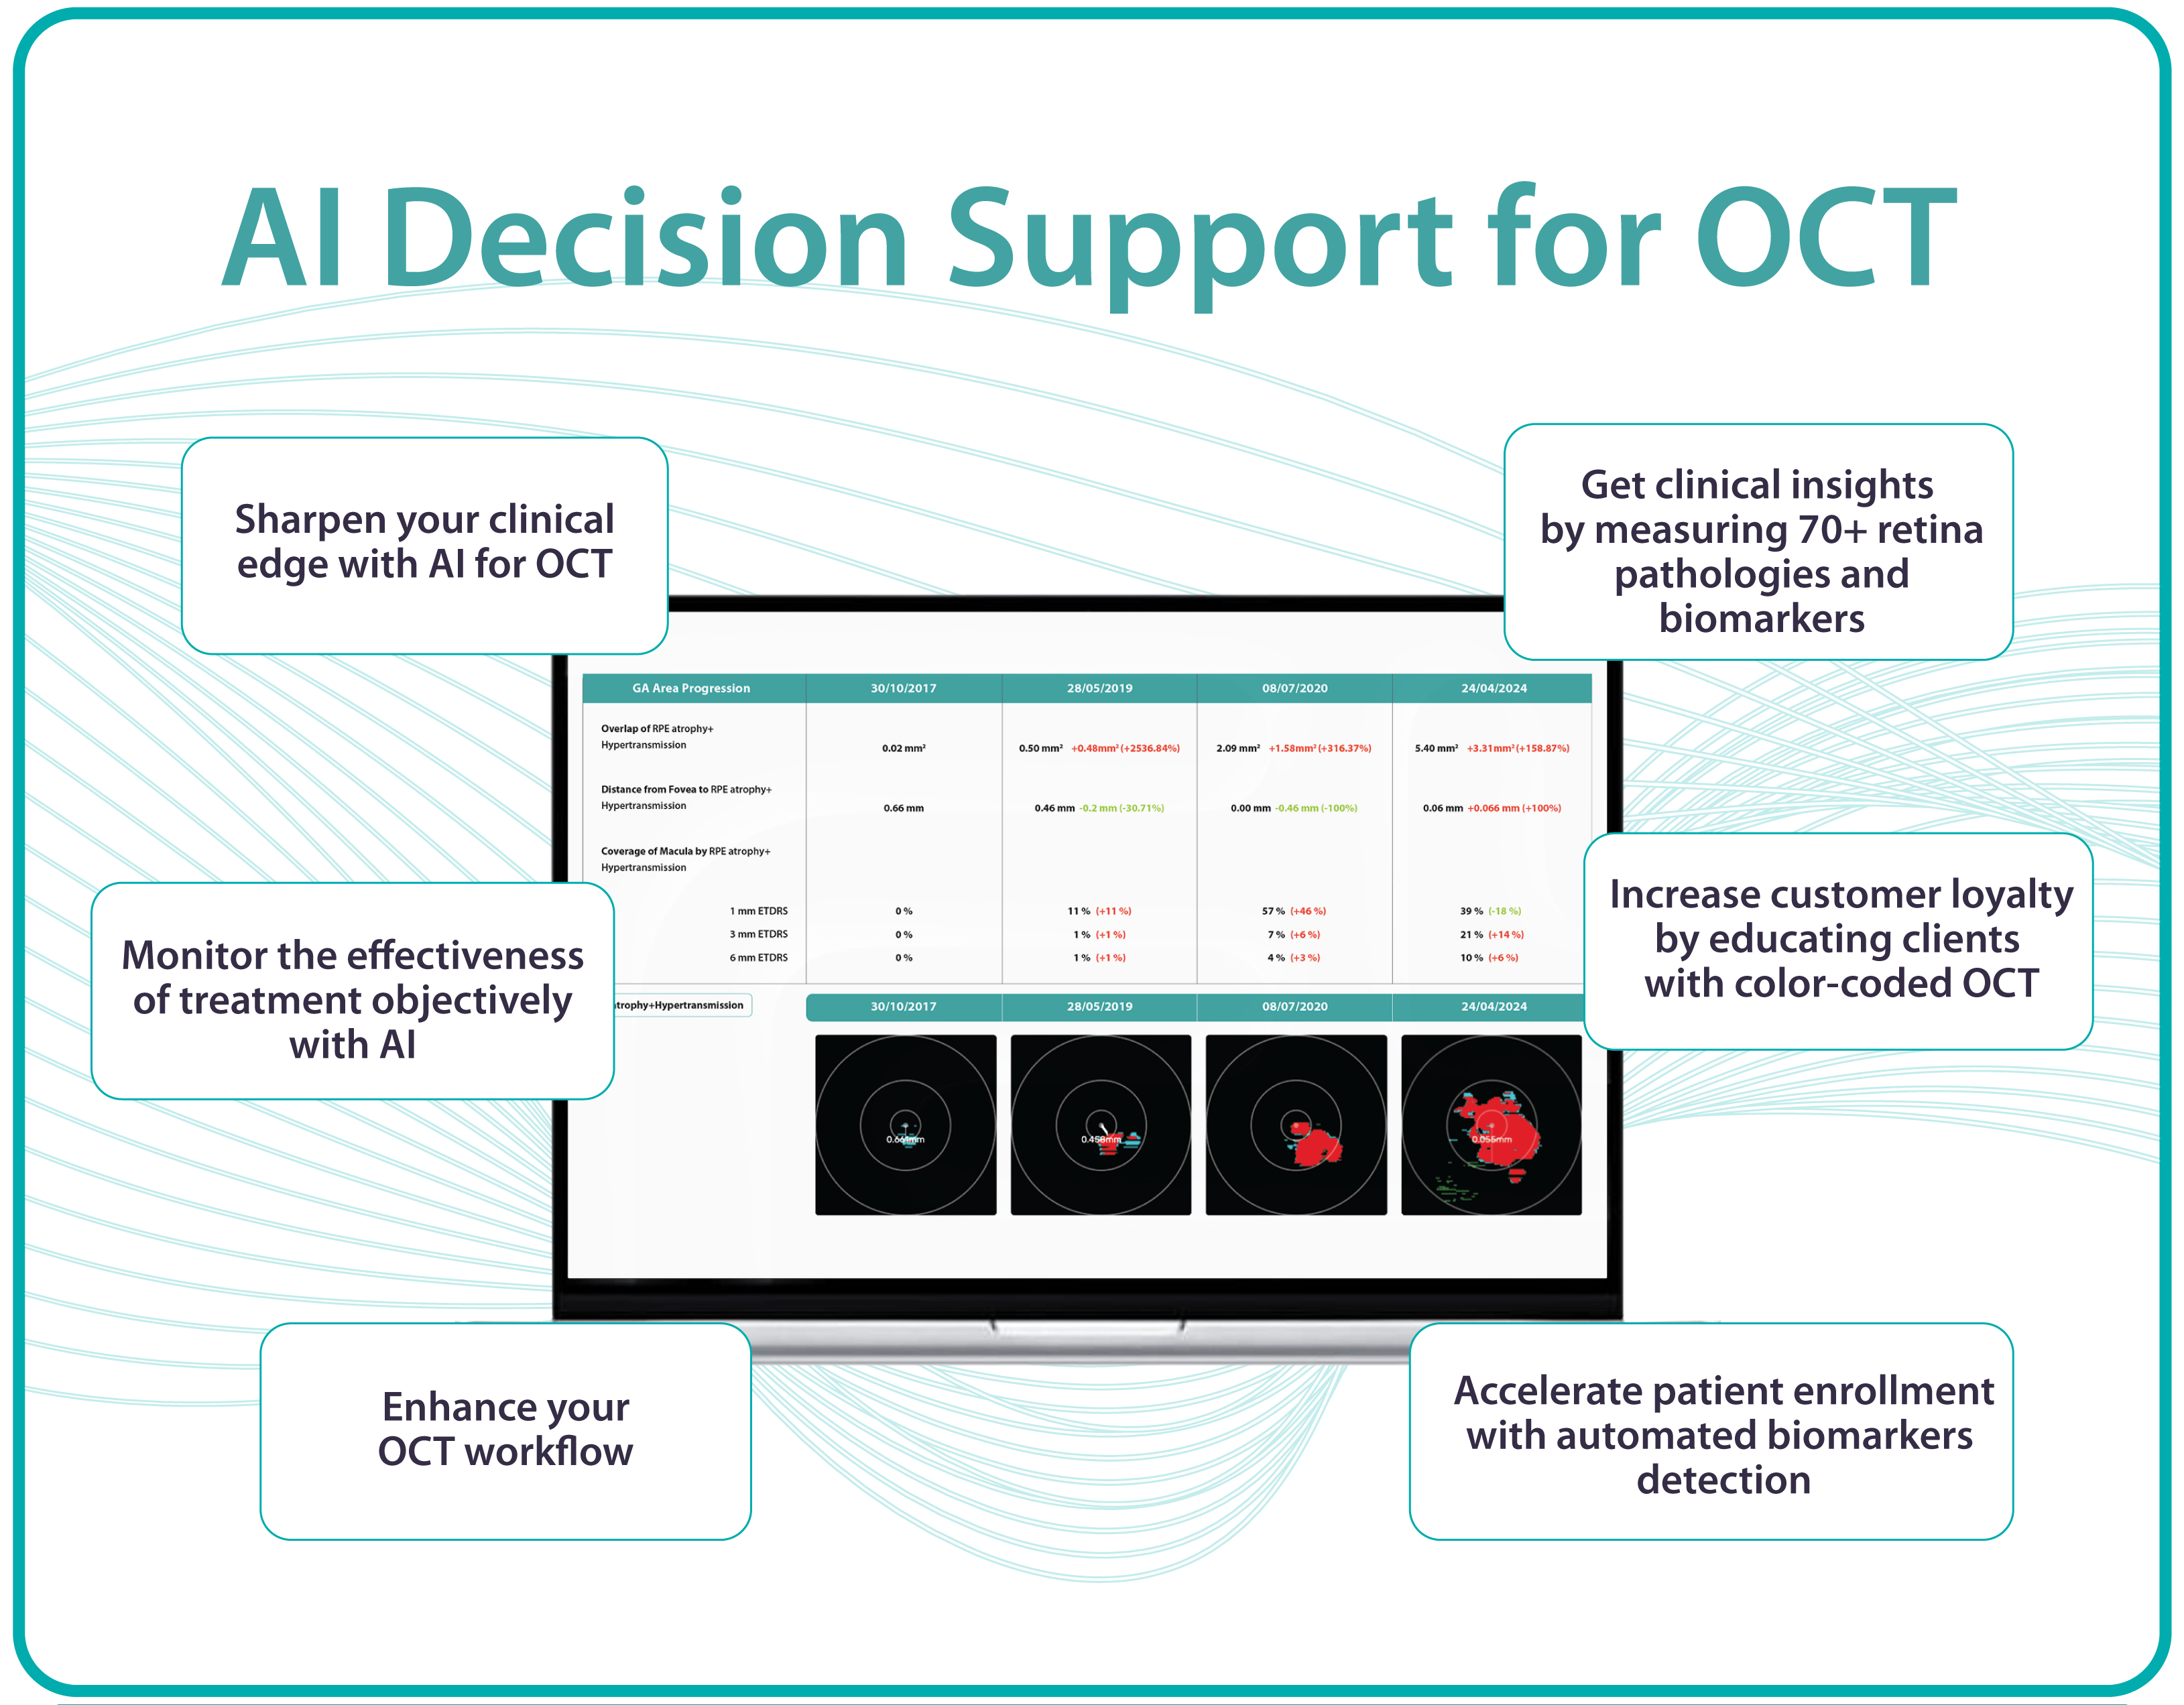

For instance, AI today can assess the early risk of glaucoma based on the GCC asymmetry measurements. Here is how AI-powered OCT workflow would look.

AI-assisted readings of OCT scans are already helping not only with pathology detection but also with the analysis of its progression or response to treatment. This represents a new approach to monitoring, where practitioners no longer need to sift through various patient notes but can directly compare reports from previous examinations and observe how, for instance, shadowing has changed in micrometers.

Altris AI’s recent survey has revealed that the key benefits of OCT technology for eye care specialists lie in treatment monitoring, patient education, and referral optimization.

Measuring treatment progress: biomarkers tracking, pathology progression

Imaging biomarkers are a particularly attractive option for clinical practice due to their non-invasive and real-time nature. Quantitative measurements of retinal thickness, fluid volume, and other biomarkers relevant to diseases like diabetic retinopathy and age-related macular degeneration aid in treatment monitoring.

OCT reports with customized measurements and selected biomarkers, retinal layers, or segments allow for precise focus on treatment monitoring and patient response to therapy. This personalized approach enhances clinical decision-making by highlighting each case’s most relevant information.

Subsequent follow-up visits will then display the most relevant picture, highlighting the most pertinent biomarkers for tracking a particular pathology (wet AMD in our example) and comparing their volume, progression, or regression through visits.

Another helpful option is retinal layer segmentation, which focuses solely on the retinal layers of interest for the specific case.

This level of customization empowers clinicians with a comprehensive yet targeted view of the patient’s condition. It saves time from manually detecting anomalies on scans and facilitates informed decision-making and personalized treatment plans.

Millions risk irreversible vision loss due to undiagnosed glaucoma, underscoring the need for improved early detection. Current tests often rely on observing changes over time, delaying treatment assessment and hindering early identification of rapid disease progression. OCT frequently detects microscopic damage to ganglion cells and thinning across these layers before changes are noticeable through other tests. However, the earliest signs on the scan can still be invisible to the human eye.

AI algorithms offer insights into glaucoma detection by routinely analyzing the ganglion cell complex, measuring its thickness, and identifying any thinning or asymmetry to determine a patient’s glaucoma risk without additional clinician effort.

In ophthalmology, AI-powered analysis of OCT scans can provide precise, quantitative measurements of retinal thickness, fluid volume, and other biomarkers relevant to diseases like diabetic retinopathy and age-related macular degeneration. These measurements can aid in diagnosis, disease staging, treatment monitoring, and prediction of treatment response.

Systems like Altris for pathology detection and segmentation enabled automated disease characterization and longitudinal monitoring of therapeutic response in AMD. Multiple studies have demonstrated the value of volumetric fluid characterization, compartment-specific OCT feature evaluation, and subretinal fibrosis and hyperreflective material quantification.